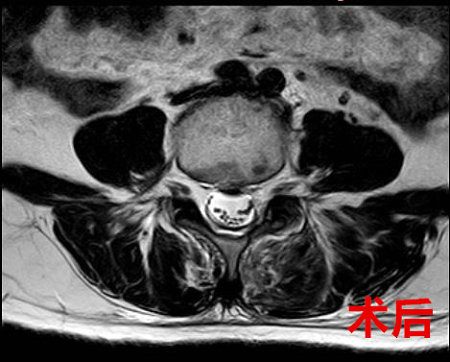

术前、术后腰椎核磁共振